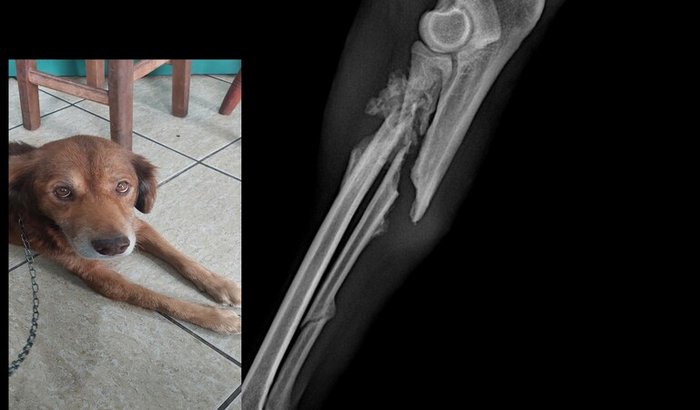

Eu sou Selma, resgatei um cão idoso na rua com a pata quebrada em três lugares, ele precisou de uma cirurgia ortopédica para voltar a andar. Em julho de 2025. Agora em agosto, retornamos com ele em outra clínica veterinária e foi constatado que ele precisará de uma nova cirurgia, pois a cirurgia anterior está causando lesões na parte traseira da patinha. Infelizmeente sozinha não consigo, e esse valor da ajuda não será o suficiente para todos os custos. Mas me ajudem, por favor!